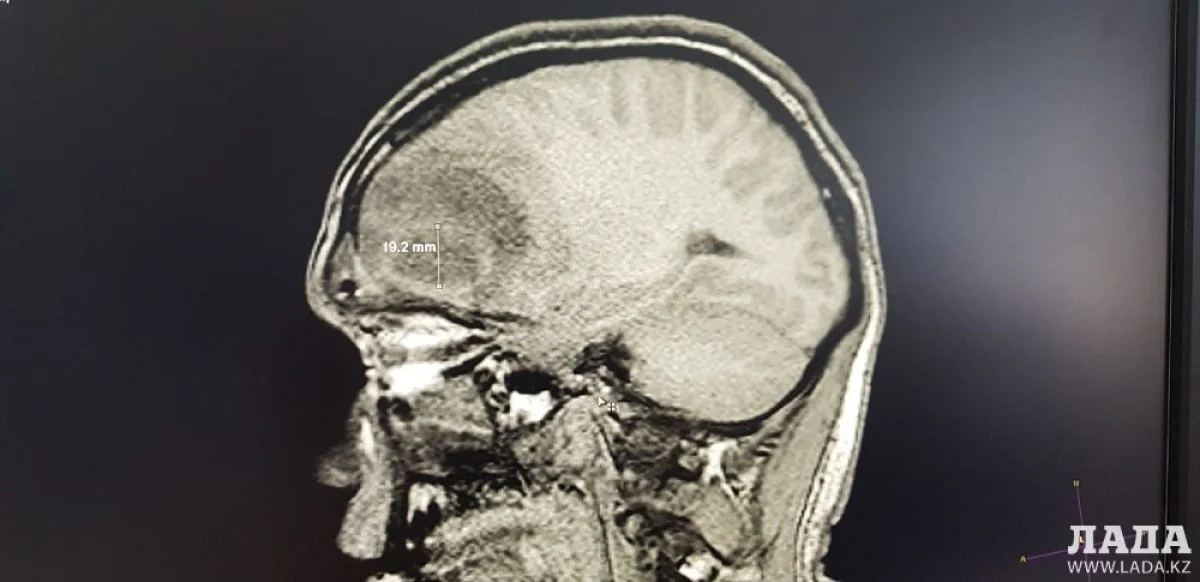

Пациент поступил в бессознательном состоянии в Мангистаускую областную больницу (МОБ) 4 апреля. У него было обнаружено гнойное образование в голове. Об этом сообщили в пресс-службе управления здравоохранения Мангистауской области.

Нейрохирург после обследования пациента обнаружил у него гнойник в головном мозге. В ходе операции, длившейся более четырех часов, объемное гнойное образование было удалено.

- После успешного удаления абсцесса состояние больного остается крайне тяжелым, но стабильным. Со слов родственников и сопровождающих, пациент около двух месяцев назад на родине получил травму головы в быту, - сообщили в пресс-службе управления здравоохранения.